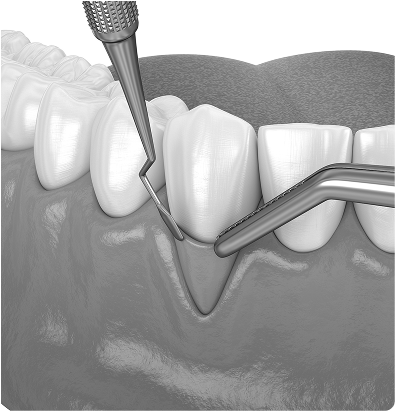

Gingivectomie

Cette intervention consiste à retirer un excès de tissu gingival, souvent dans un but fonctionnel ou esthétique. Elle permet, par exemple, d’uniformiser la ligne des gencives ou de faciliter l’accès pour l’hygiène.